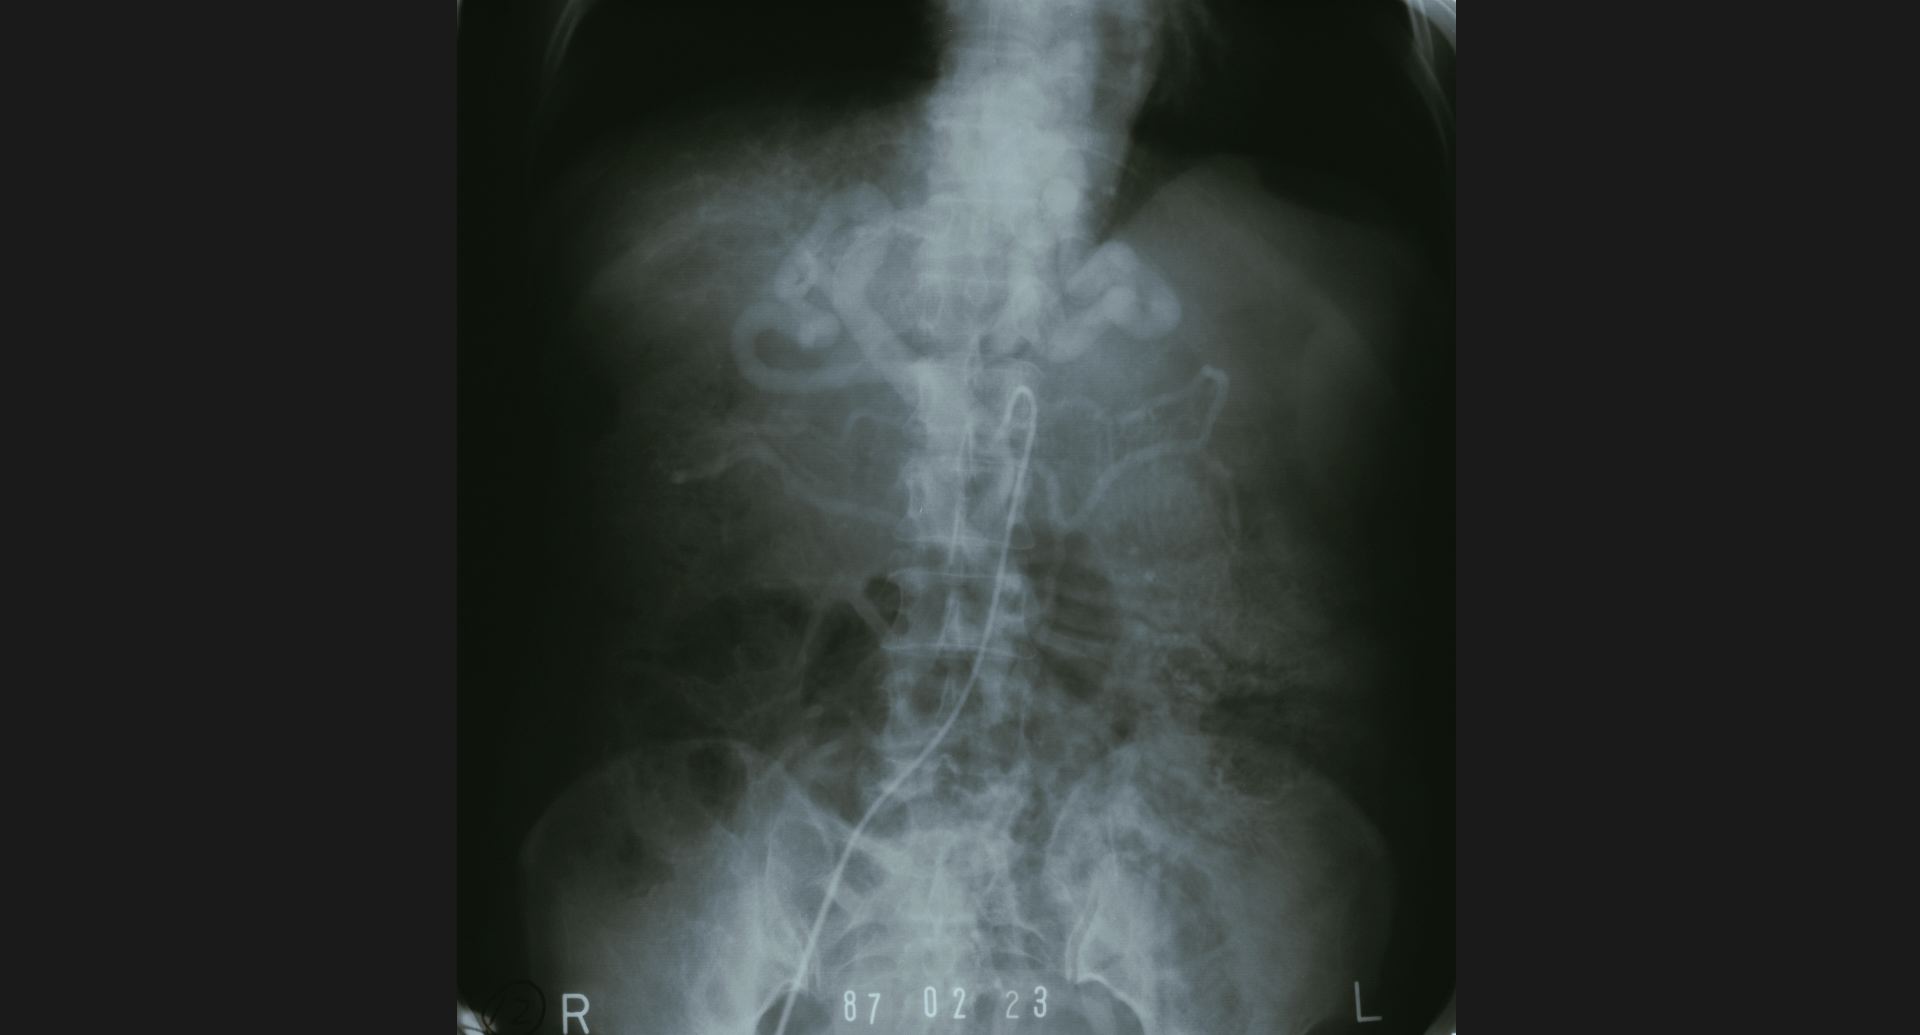

fig.10(99KB) :SMA thrombosis (angiography)

閉塞部位。腸管壁の細かい動脈。